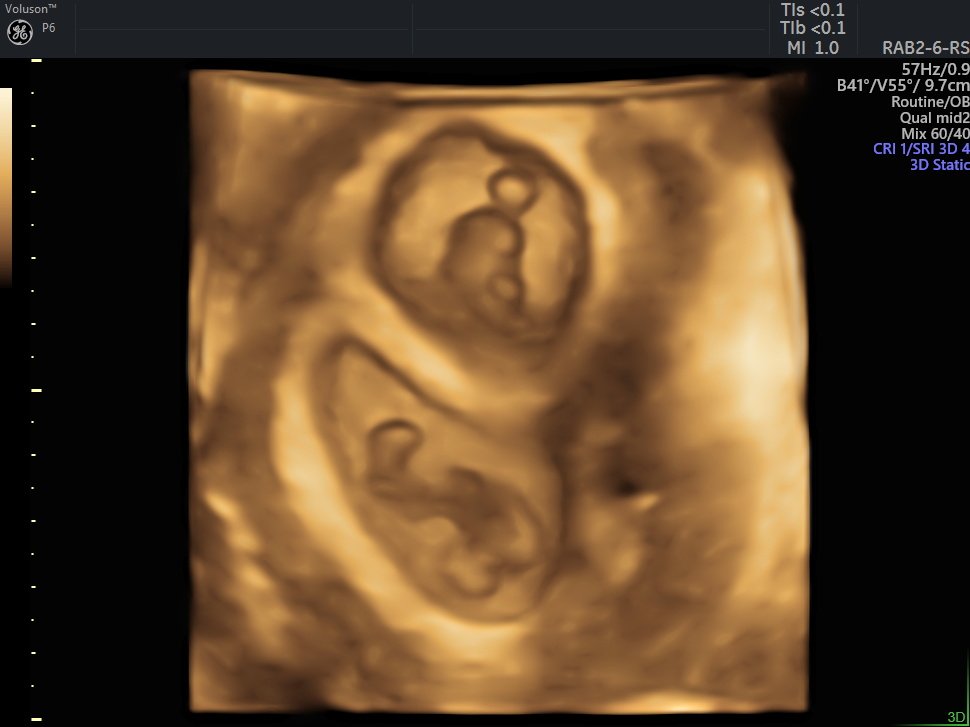

4 Boyutlu (Renkli) Ultrason ve Doppler Ultrasonografi

4 D Ultrasonografi